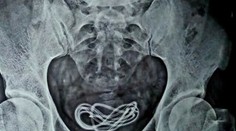

Nabíjačka Muž prehltol nabíjačku na mobil. Keď lekár zistil, kam sa až dostala, zostal v šoku Róbert Ďurkáč 10. 6. 2020